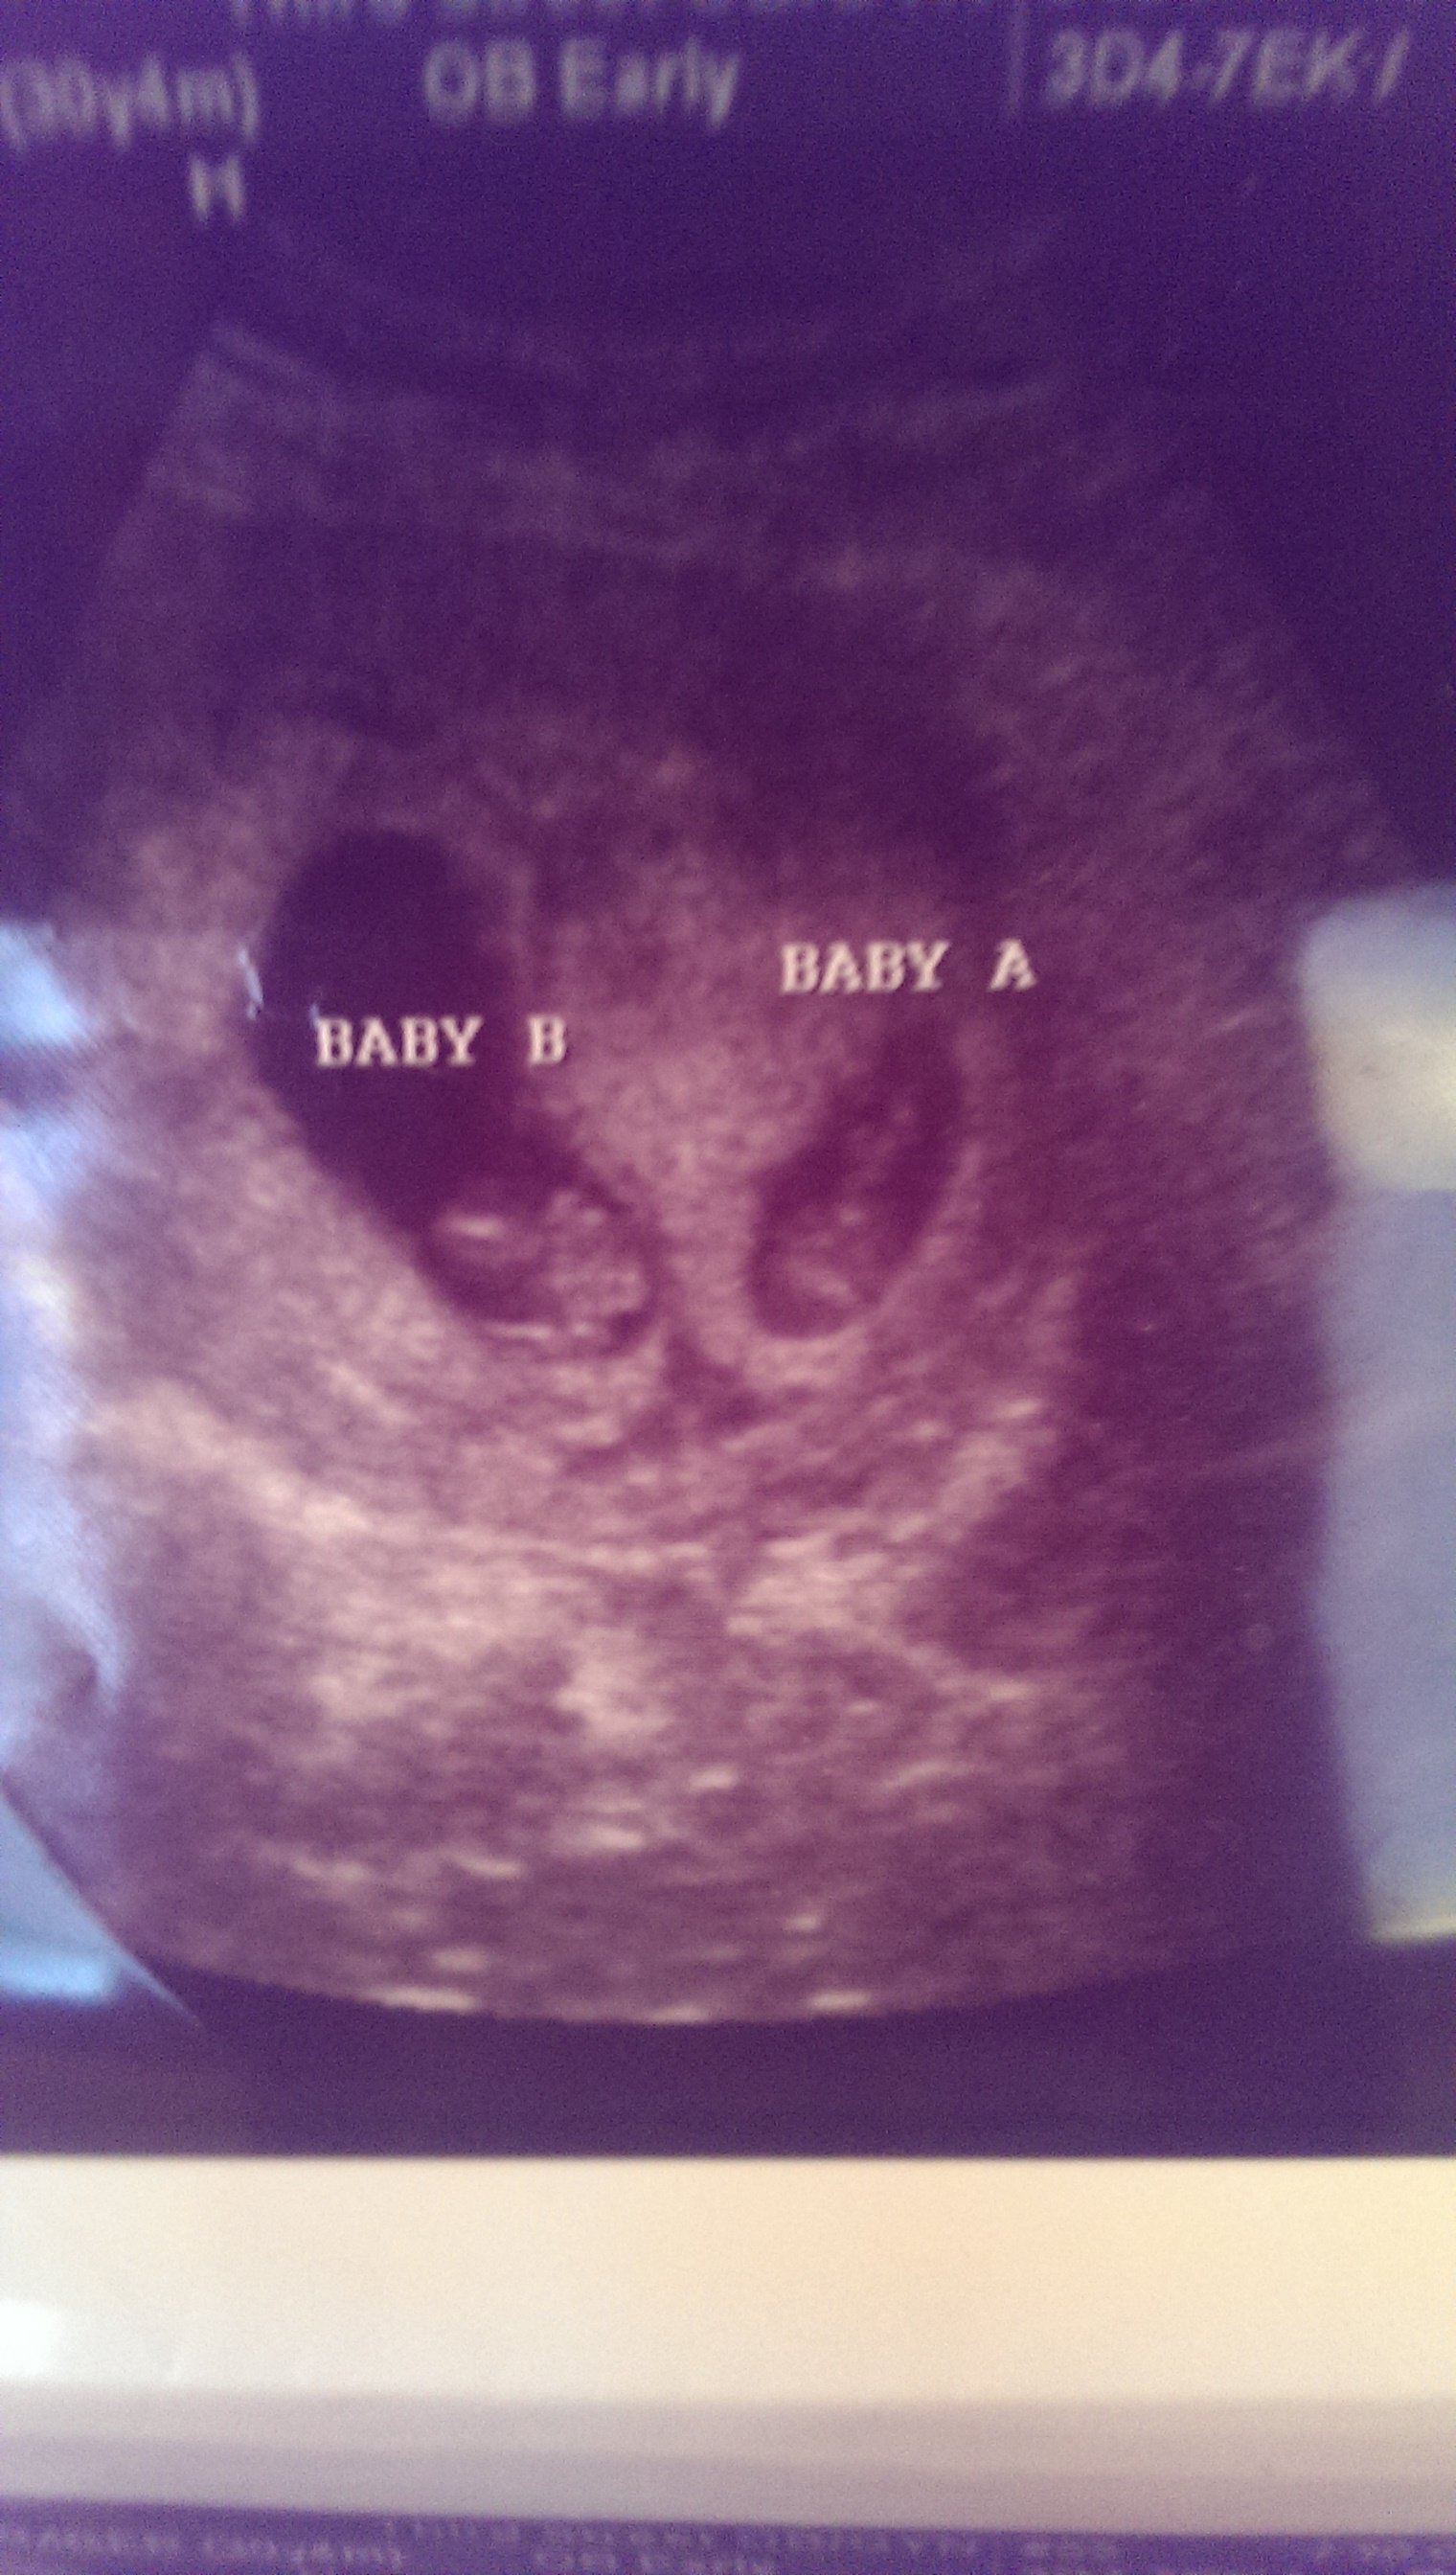

Everyone was in for a surprise today- went in for a dating u/s and my surprise natural BFP ended up being double trouble! Both measuring 7w1d, so my official EDD is 11/18! I was only off 1 day, LMP was off by over a week.